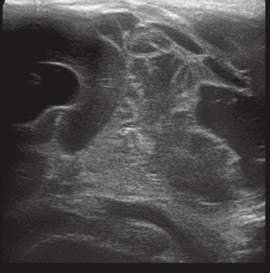

Neonatology PVHI Thalamus 5 Image